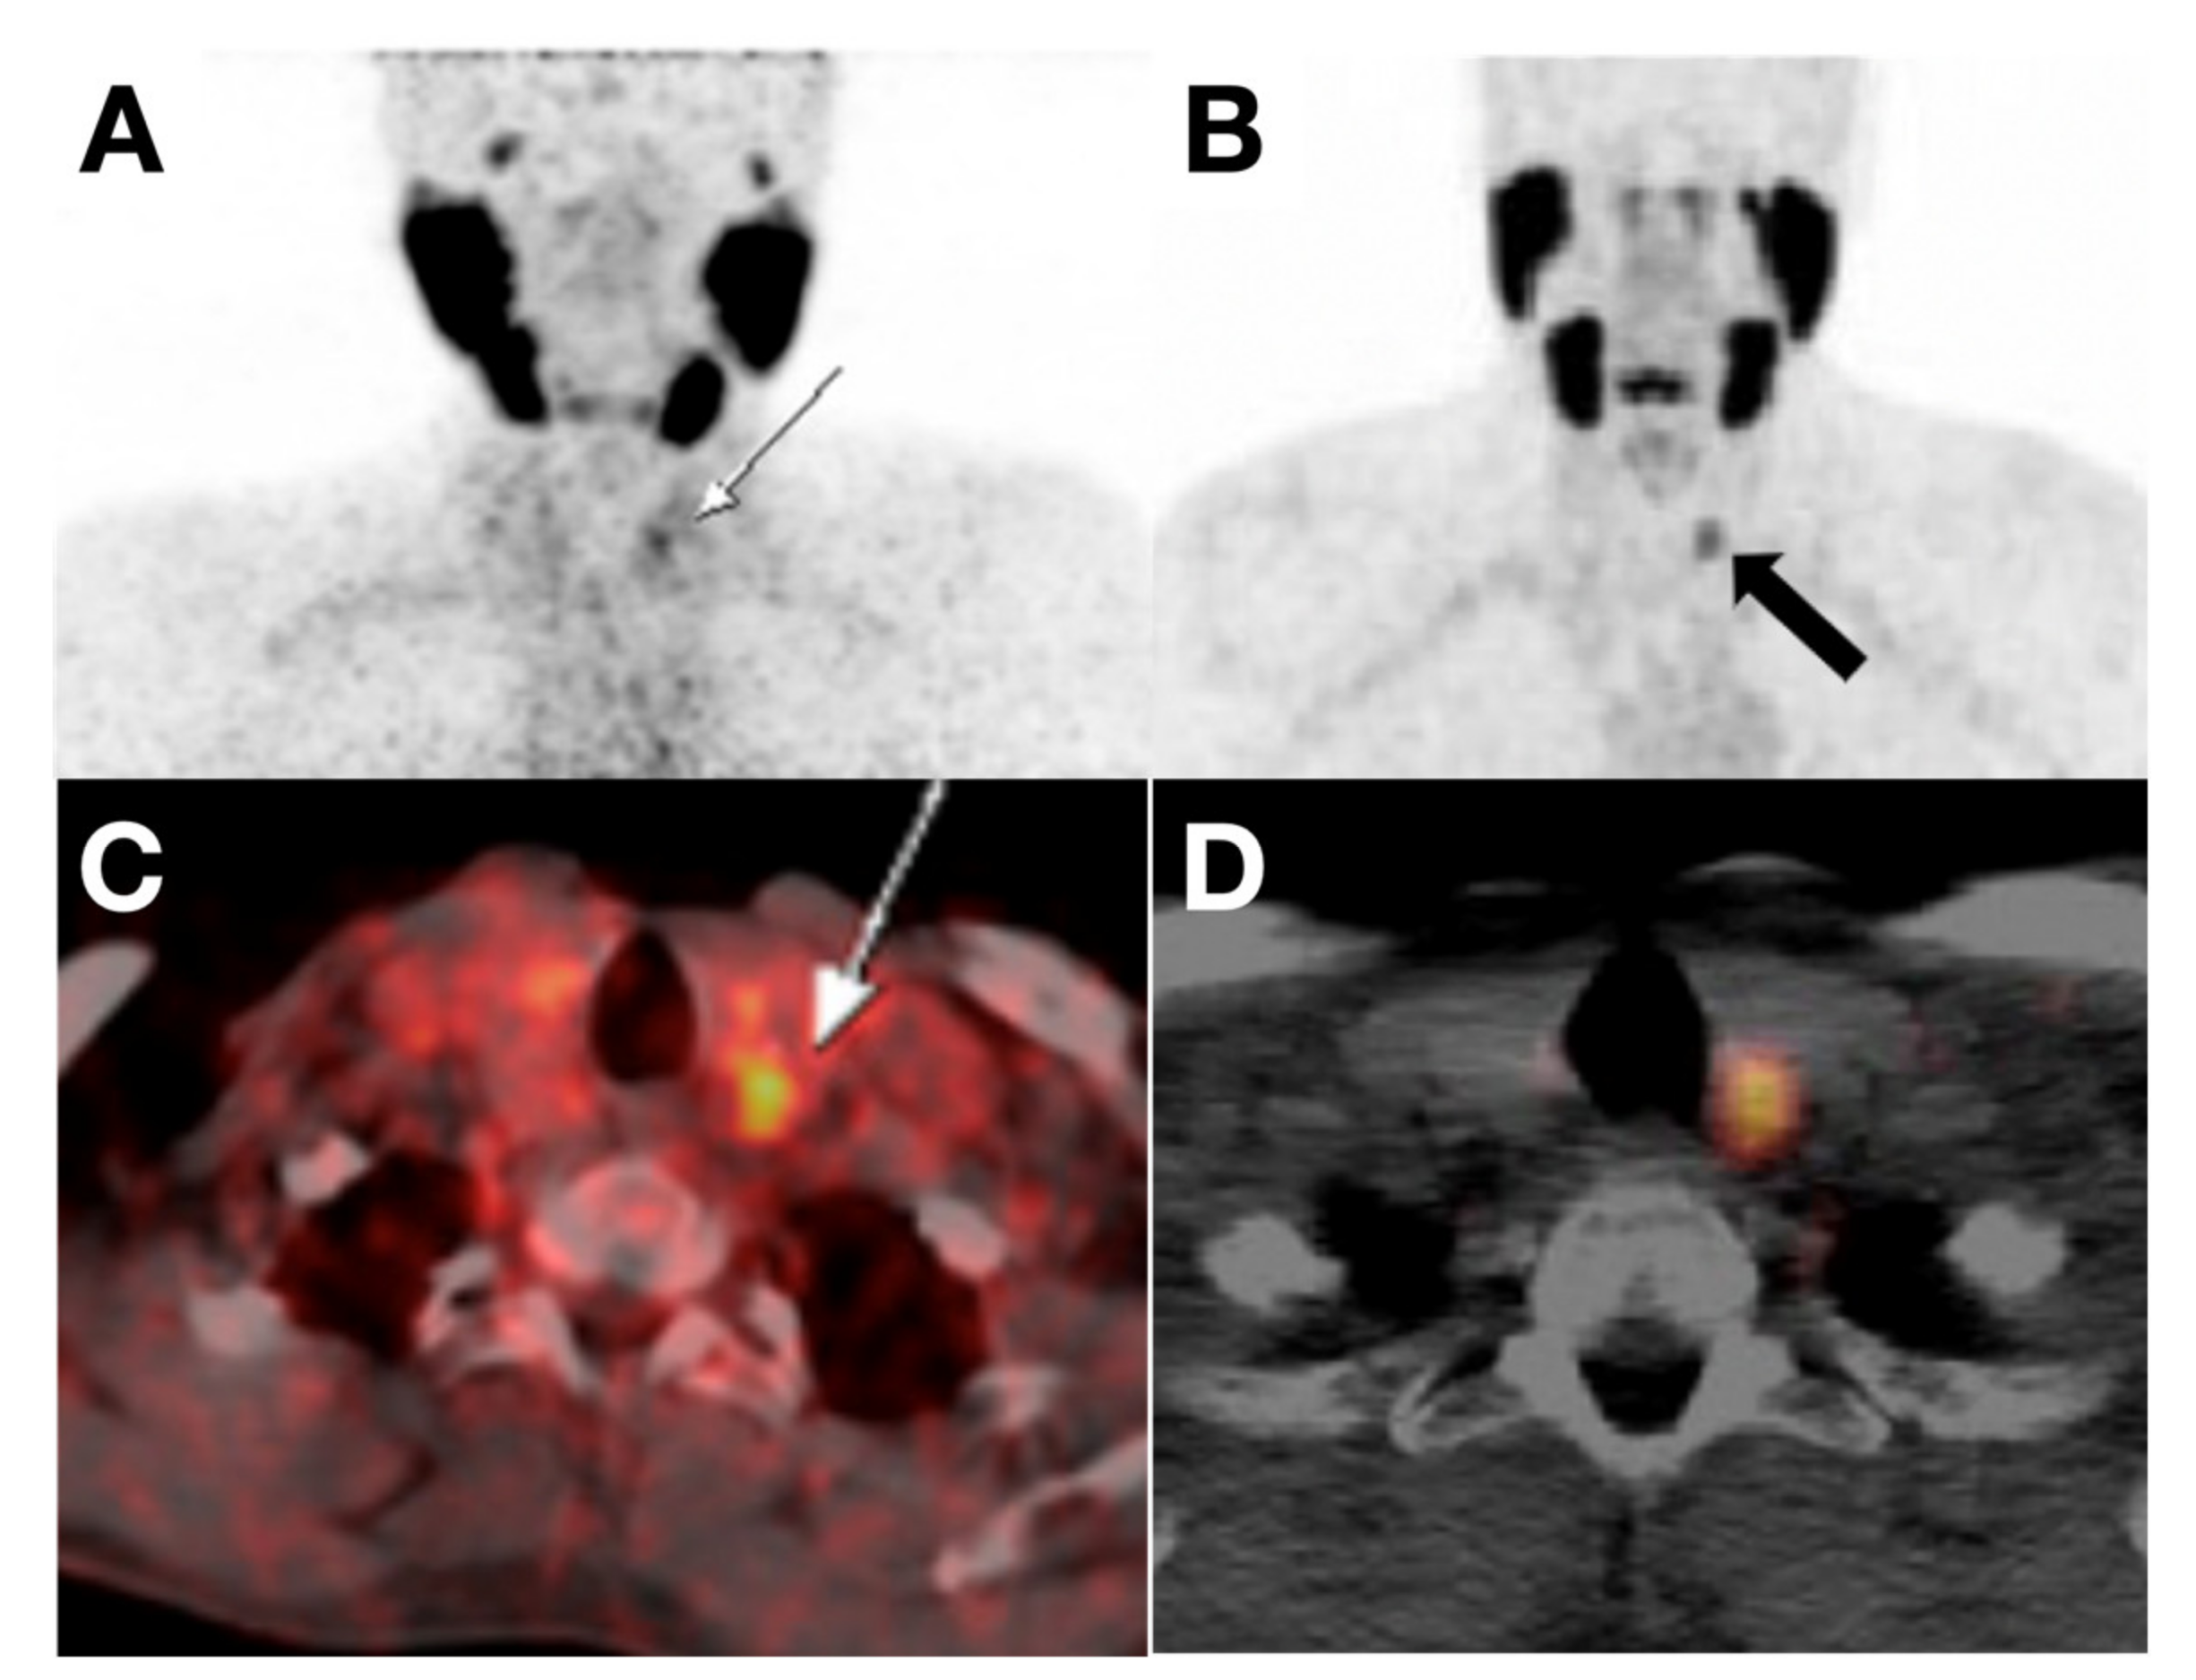

- Dittmann, M.; Carvalho, J.M.G.; Rahbar, K.; Schäfers, M.; Claesener, M.; Riemann, B.; Seifert, R. Incremental Diagnostic Value of [18F]Tetrafluoroborate PET-CT Compared to [131I]Iodine Scintigraphy in Recurrent Differentiated Thyroid Cancer. Eur. J. Nucl. Med. Mol. Imaging 2020, 47, 2639–2646. [Google Scholar] [CrossRef]

- Samnick, S.; Al-Momani, E.; Schmid, J.-S.; Mottok, A.; Buck, A.K.; Lapa, C. Initial Clinical Investigation of [18F]Tetrafluoroborate PET/CT in Comparison to [124I]Iodine PET/CT for Imaging Thyroid Cancer. Clin. Nucl. Med. 2018, 43, 162–167. [Google Scholar] [CrossRef]